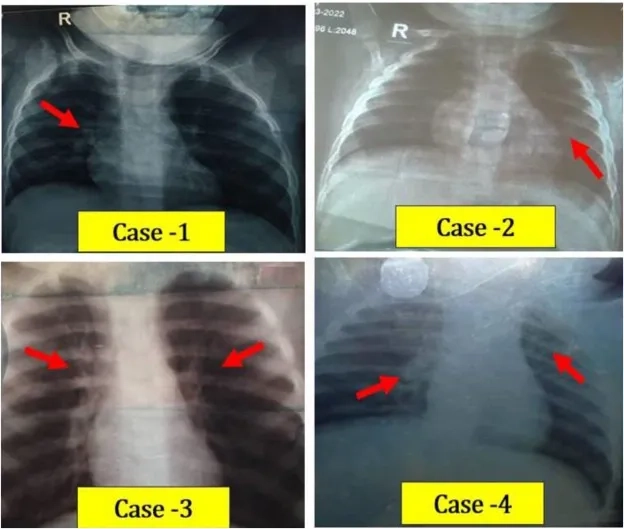

Image description of human bocavirus infection

Human Bocavirus is a small DNA virus causing respiratory infections mainly in children, leading to mild to moderate symptoms such as cough, fever, and fatigue.